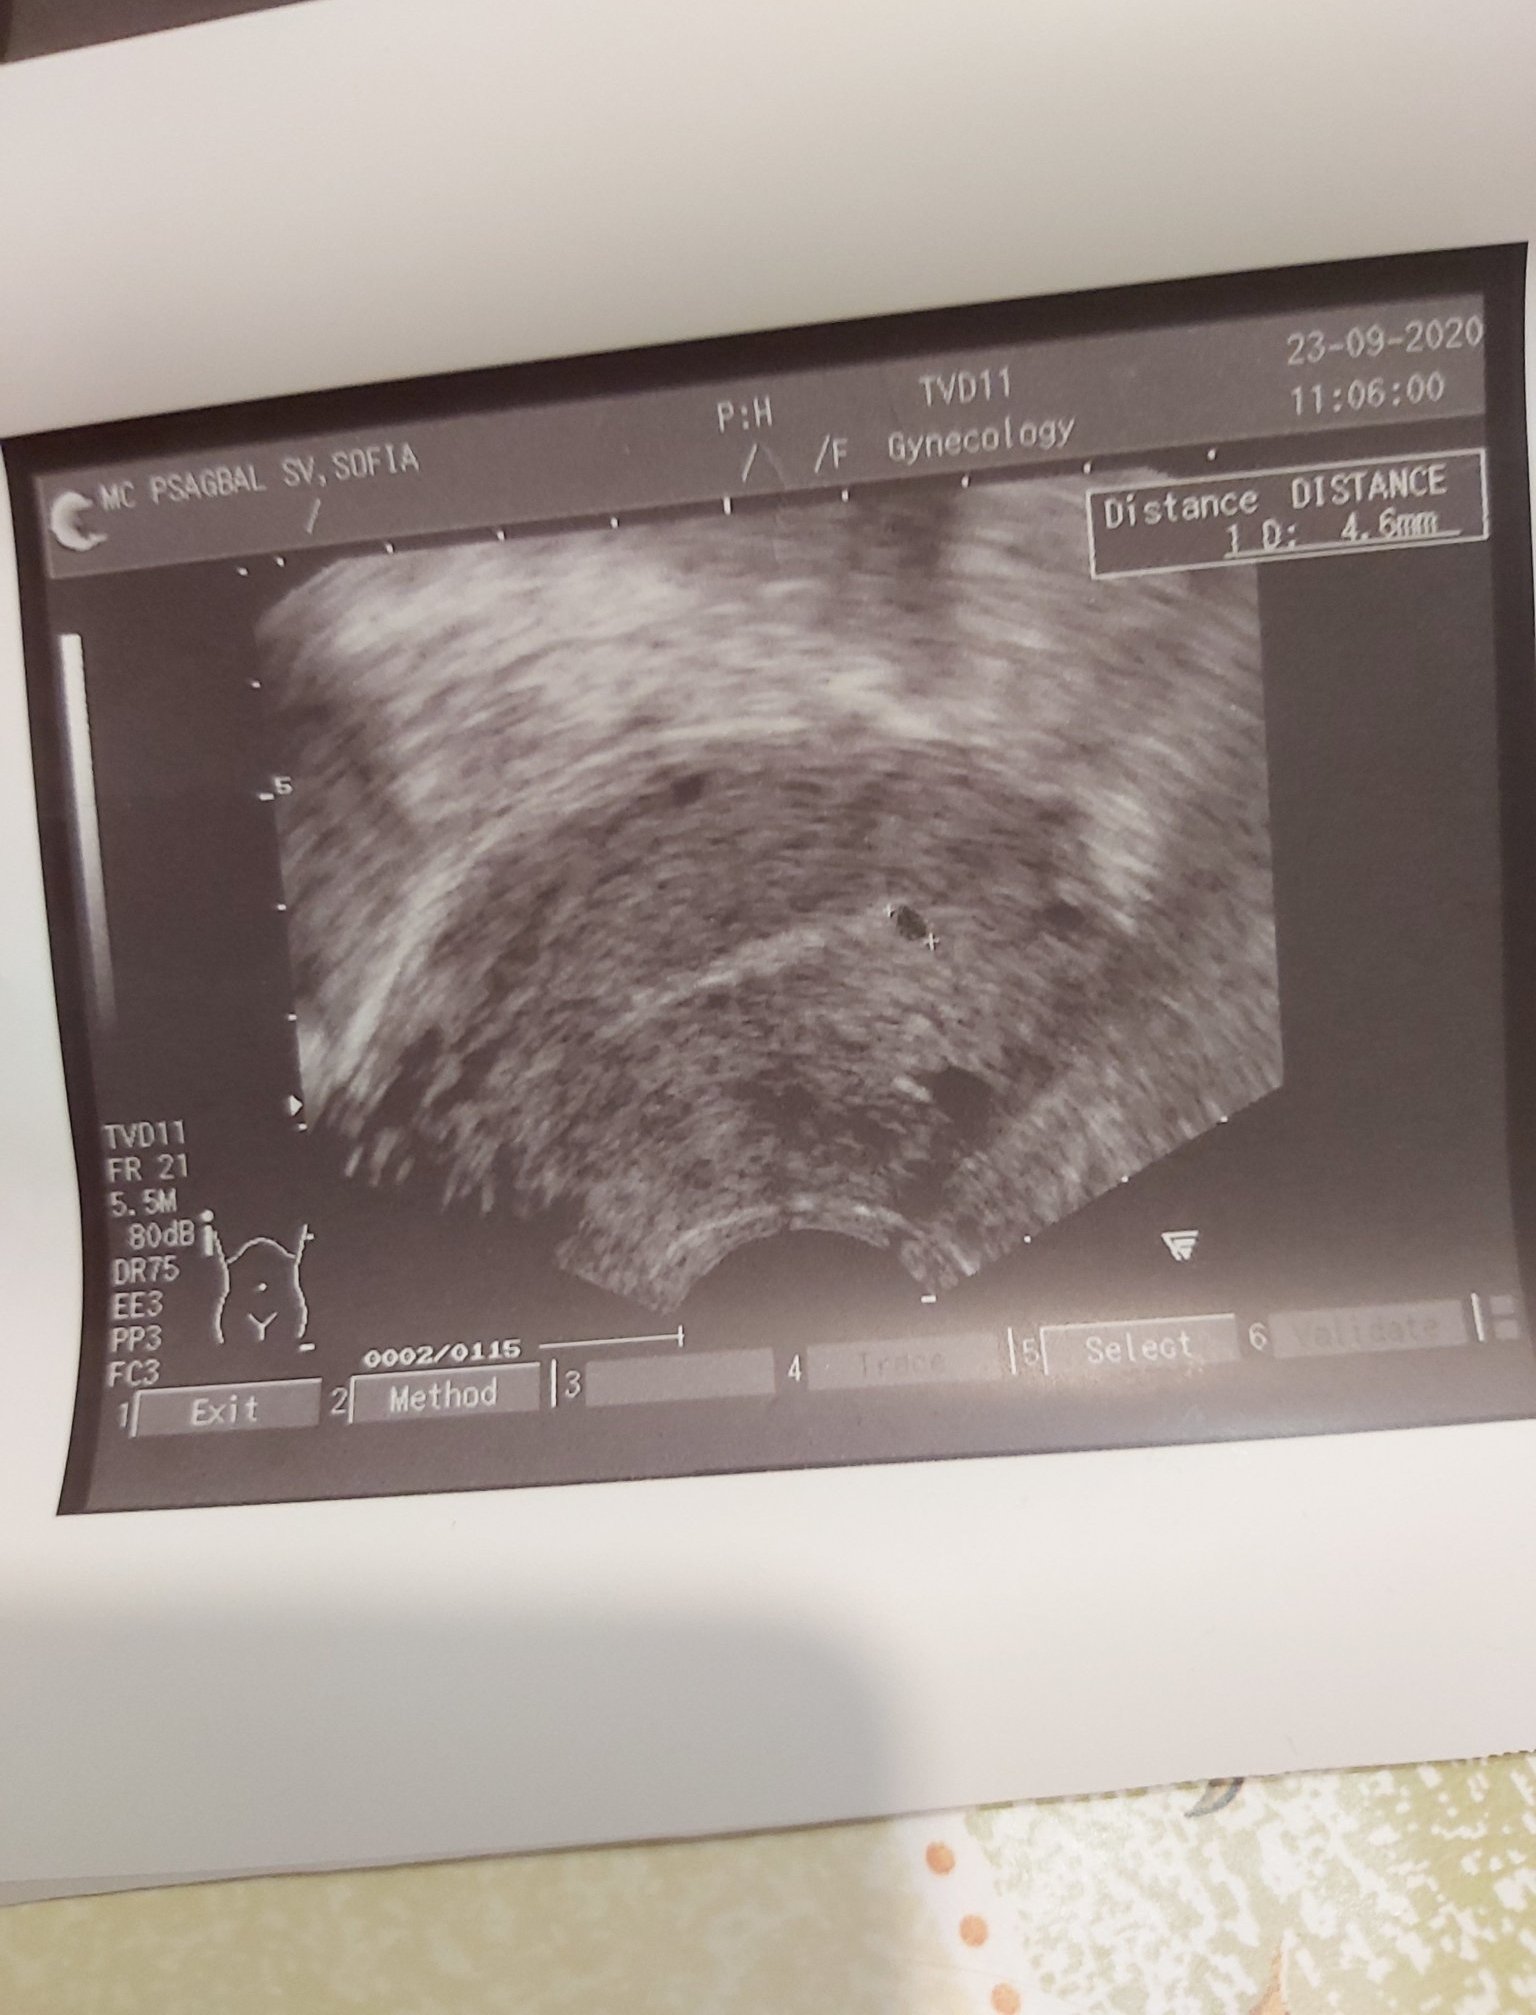

Ето и снимки .Кажете момичета как ги тълкувате.Желанието не позволява да губя надежда

На мен ми прилича на плоден сак. Но не съм специалист.